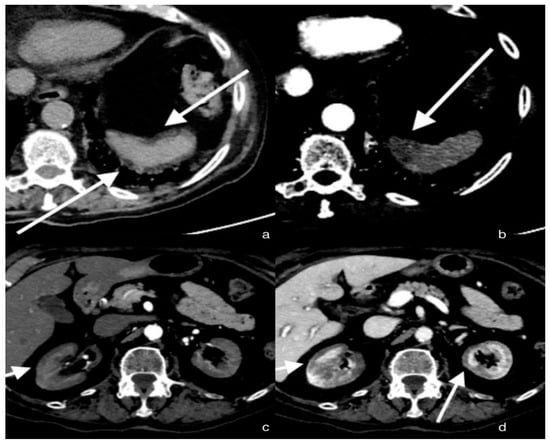

A total-body CT scan was performed after the intravenous administration of a contrast medium under a specific study protocol to assess the aorta and vessels of the lower limb conditions, for the patient’s clinical condition and the elevated D-dimer. The CT scan demonstrated opacification of the left common iliac artery and a filiform left superficial femoral artery. Reduced opacification of the left femoral vein was observed at a later stage of the research. Moreover, a peripheral hypodense flap of both kidneys was observed during the contrast phases, likely as a result of renal cortical necrosis. In addition, a small area of necrotic hypoperfusion, which was located at the upper pole of the spleen, was observed as well. Furthermore, diffuse ground-glass opacity (GGO) can be observed on CT imaging of the lungs, associated with crazy-paving patterns. The total severity score was 18/20 s (according to Chung et al.) [12] (Figure 1).

Figure 1. Axial sections of the abdomen in the basal (a) and arterial (b) phases; the arrows show a small hypo-dense subcapsular area well delimited by the splenic capsule. This area in the arterial phase remains as a hypodense lesion. Lack of enhancement. Axial section of the abdomen in the arterial (c) and portal venous (d) phases; the arrows show a non-enhancing renal cortex. Images show a normal enhancing renal medulla (acute cortical necrosis), and the hypodense cortex is surrounded by a thin peripheral rim of enhancement in the portal venous phase.

Concerning renal cortical necrosis, contrast-enhanced CT demonstrates a non-enhancing renal cortex and a normal enhancing renal medulla (reverse rim sign) [18]. CT performed during the portal venous phase represents the imaging exam of choice for spleen infarction and typically demonstrates, in the case of peripheral infarction, a wedge-shaped hypo-enhancing region [19].